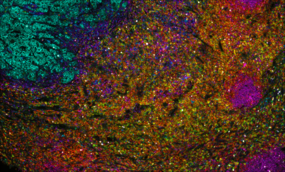

Invasive ductal carcinoma Grade I stained with 6-plex mIF.

At Fortis, we use TSA on slides produced for the Akoya PhenoImager™ HT using Opal™ reagents to generate up to 6-plex images.